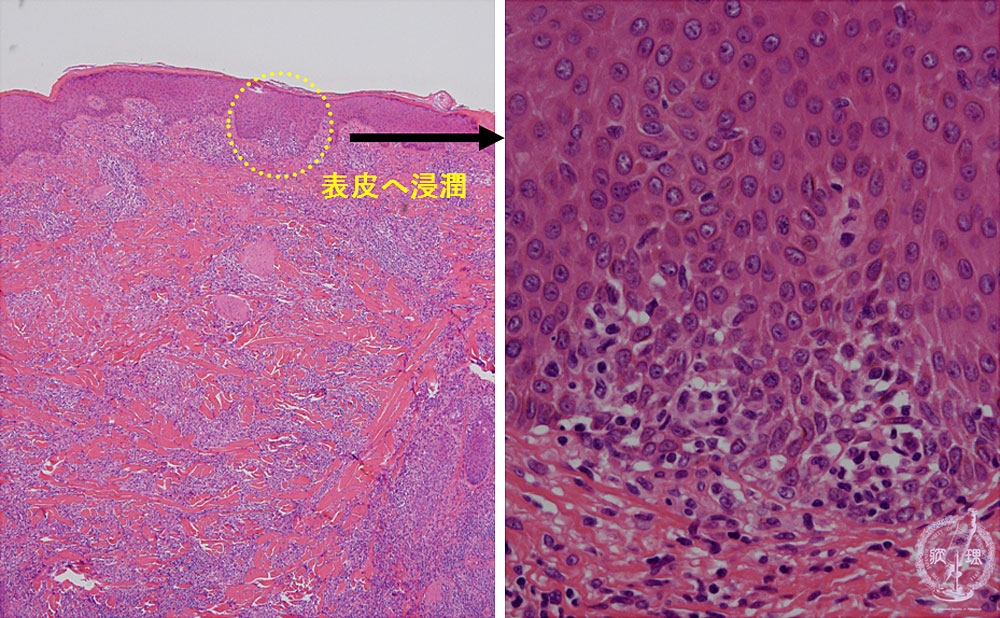

UMIN WWW LIBRARY OF PATHOLOGY。